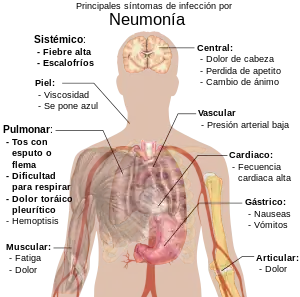

Los casos de neumonía infecciosa a menudo presentan una tos que produce un esputo (flema) de color marrón o verde y una fiebre alta que puede ir acompañada de escalofríos febriles. La disnea (dificultad respiratoria) es el signo temprano más específico y sensible. El dolor torácico pleurítico también es común, (dolor agudo o punzante que aparece o empeora con la tos y con la respiración profunda.) Los enfermos de neumonía pueden toser sangre (hemoptisis), sufrir dolores de cabeza o presentar una piel sudorosa y húmeda. Otros síntomas posibles son falta de apetito, cansancio, cianosis, náuseas, vómitos y dolores articulares o musculares. Las formas menos comunes de neumonía pueden causar otros síntomas, por ejemplo, la neumonía causada por Legionella, ya que puede causar dolores abdominales y diarrea,[12] mientras que la neumonía provocada por tuberculosis o Pneumocystis puede causar únicamente pérdida de peso y sudores nocturnos. En las personas mayores, la manifestación de la neumonía puede no ser típica. Pueden desarrollar una confusión nueva o más grave, o experimentar desequilibrios, provocando caídas.[13] Los niños con neumonía pueden presentar muchos de los síntomas mencionados, pero en muchos casos simplemente están adormecidos o pierden el apetito.

Los síntomas de la neumonía requieren una evaluación médica inmediata. La exploración física por parte de un asistente sanitario puede revelar fiebre o a veces una temperatura corporal baja, una velocidad de respiración elevada (taquipnea), una presión sanguínea baja (hipotensión), un ritmo cardíaco elevado (taquicardia), o una baja saturación de oxígeno (SatO2), que es la cantidad de oxígeno en la hemoglobina bien revelada por pulsioximetría o por gasometría arterial (GASA). Los enfermos que tienen dificultades para respirar (disnea), están confundidos o presentan cianosis (piel azulada) y necesitan de atención inmediata.

Signos y síntomas

Los siguientes síntomas pueden estar relacionados con la enfermedad:[28]

- Las personas afectadas de neumonía a menudo tienen tos que puede producir una expectoración de tipo mucopurulento (amarillenta), fiebre alta que puede estar acompañada de escalofríos. Limitación respiratoria también es frecuente así como dolor torácico de características pleuríticas (aumenta con la respiración profunda y con la tos). También pueden tener hemoptisis (expectoración de sangre por la boca durante episodios de tos) y disnea. Suele acompañarse de compromiso del estado general (anorexia, astenia y adinamia).

- Al examen físico general es probable encontrar taquicardia, taquipnea y baja presión arterial, ya sea sistólica o diastólica.